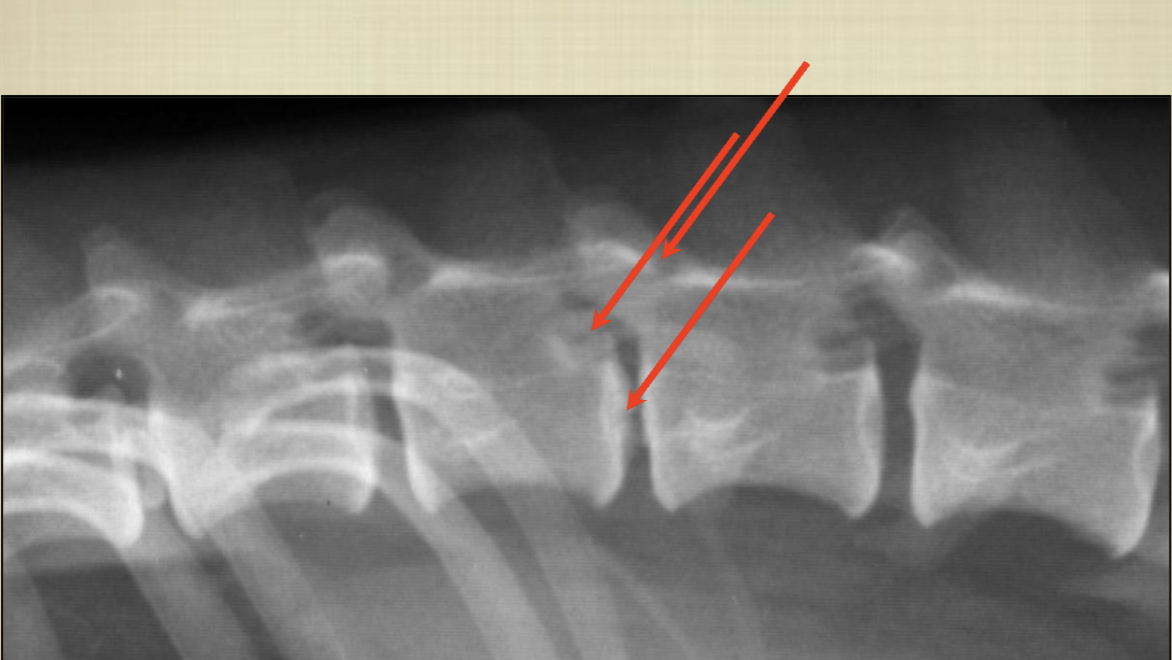

What are these arrows identifying in this radiograph (clockwise from the top)?

A

top: spinous process

next: articular facets

middle: intervertebral foramen

next: disc space

bottom: transverse process